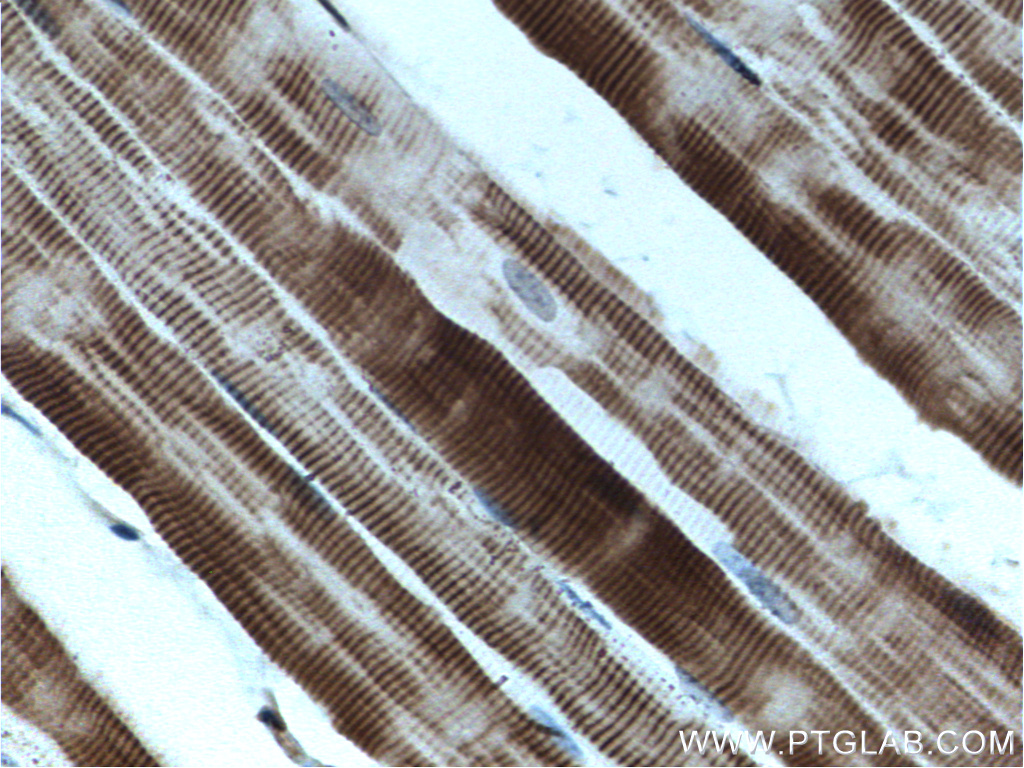

| Positive IHC detected in | mouse skeletal muscle tissue Note: suggested antigen retrieval with TE buffer pH 9.0; (*) Alternatively, antigen retrieval may be performed with citrate buffer pH 6.0 |

MYOT (myotilin) is a structural protein of the striated muscle Z-discs. It interacts with both actinin and filamin, forming a complex to maintain structural stability of muscles. In adult tissues, myotilin is mainly expressed in skeletal and cardiac muscles and in the peripheral nerves. Missense mutations of myotilin cause limb girdle muscular dystrophy 1A and some other myopathy. Two isoforms of MYOT exist due to the alternative splicing. This antibody can detect both of isoforms around 57 kDa and 35 kDa.